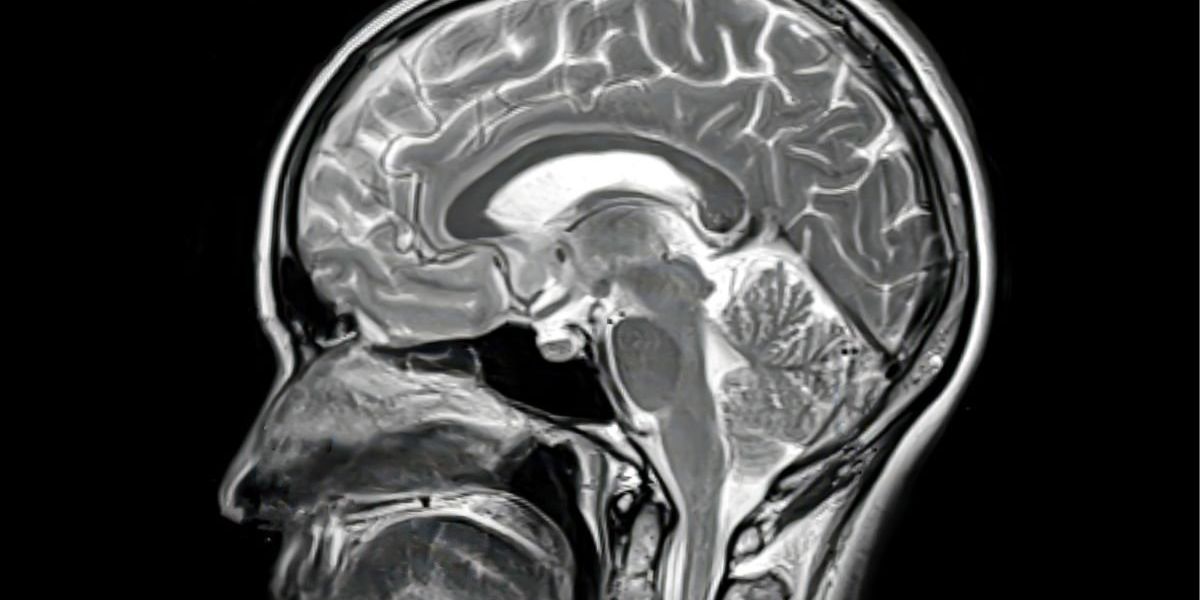

Elevated levels of tau protein in the brain could signal a higher risk of brain decline